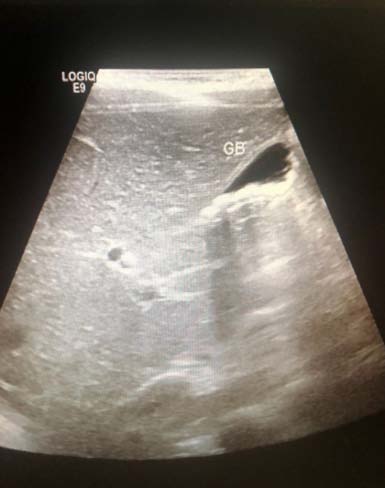

? Dedifferentiated liposarcoma ? Myxoid liposarcoma ? Pleomorphic liposarcoma ? Myxoid pleomorphic liposarcomaIn atypical lipomatous tumour/well differentiated liposarcoma adipocytic variant consists out of cells that vary substantially in size as well as cells that have Dedifferentiated liposarcoma can arise as a synchronous lesion in 90% of cases and as metachronous lesion in 10% of cases 6 . These tumours exhibit a wide morphological spectrum and histologically show areas of high grade, poorly differentiated sarcoma resembling high-grade myxofibrosarcoma, fibrosarcoma, malignant solitary fibrous tumour or pleomorphic sarcoma not otherwise specified. Dedifferentiated liposarcomas can be of variable histological grade 5 . Dedifferentiated liposarcomas is an aggressive disease, arising most commonly in the retroperitoneum and is associated with high rates of local and metastatic recurrence and disease specific mortality 7 Use of the term atypical lipomatous tumour is determined by tumour location and resectability. In locations such as the retroperitoneum, it is usually impossible to obtain a wide tumour free surgical margin of more than 2cm, thus local recurrence is common and leads to mortality, seen in the absence of dedifferentiation or metastases The introduction of computed tomography (CT), magnetic resonance imaging (MRI), and ultrasonography have greatly enhanced our capability to make the diagnosis of abdominopelvic neoplasms and determine and direct treatment, as well as observe the progress of the neoplasm and effect of treatment over time. Identification of a retroperitoneal mass at imaging is a challenging task for radiologists, however the presence of fat within a retroperitoneal lesion is helpful in refining the differential diagnosis 9 ? On ultrasound appearance it is hyperechoic and may demonstrate posterior acoustic shadowing . It is easy to recognize fat within a lesion due to its characteristic imaging appearance: